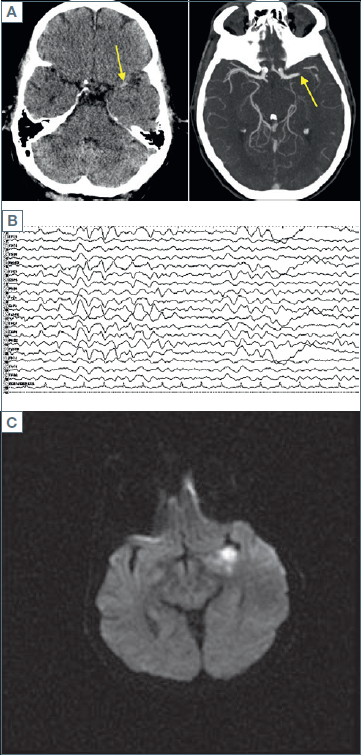

The medical history was negative for the major cardiovascular risk factors. When he presented to the hospital, the score on the National Institutes of Health Stroke Scale (NIHSS) was 13 (scores range from 0 to 42, with higher numbers indicating greater stroke severity) 1, and computed tomography (CT) and CT angiography of the cerebral arteries showed a infarction of the left middle cerebral artery with a partially occlusive thrombus in the left carotid artery at the cervical bifurcation and occlusion of the left middle artery (image A). Blood test showed D-dimer 52 ng/ml, fibrinogen 370 mg/dl, 9900 white-cell count per mm3 with lymphopenia. Electrocardiogram showed sinus rhythm. Antiplatelet therapy was started (aspirin 100 mg daily). Stroke workup with echocardiography and carotid ultrasound of the head and neck did not reveal the source of the thrombus.

On arrival, neurology consultant observed right greater than left cogwheel rigidity and myoclonus (left greater than right). Electroencephalogram was performed and it showed diffuse theta slowing (image B), frequent and low amplitude isolated generalized discharges, and frequent brief periods of 1 Hz generalized rhythmic delta activity with sharp contouring and bilateral frontal predominance.

Electroencephalogram showed a general excess of beta-rhythm, as seen with benzodiazepine treatment as well as infrequent, short-lasting rhythmic left temporal delta activity, never exceeding 10 s. The day after admission, a brain magnetic resonance imaging (MRI) showed an asymmetric FLAIR (Fluid-attenuated inversion recovery) hyperintensity of the left medial temporal cortex (image C) associated with mild gyral expansion without any diffusion restriction or contrast enhancement.

Figure 1. A) CT angiography of the cerebral arteries showed (blue line) occlusion of the left middle cerebral artery; B) Electroencephalogram showed diffuse theta slowing; C) Hyperintensity in left medial temporal lobe on diffusion weighted imaging.